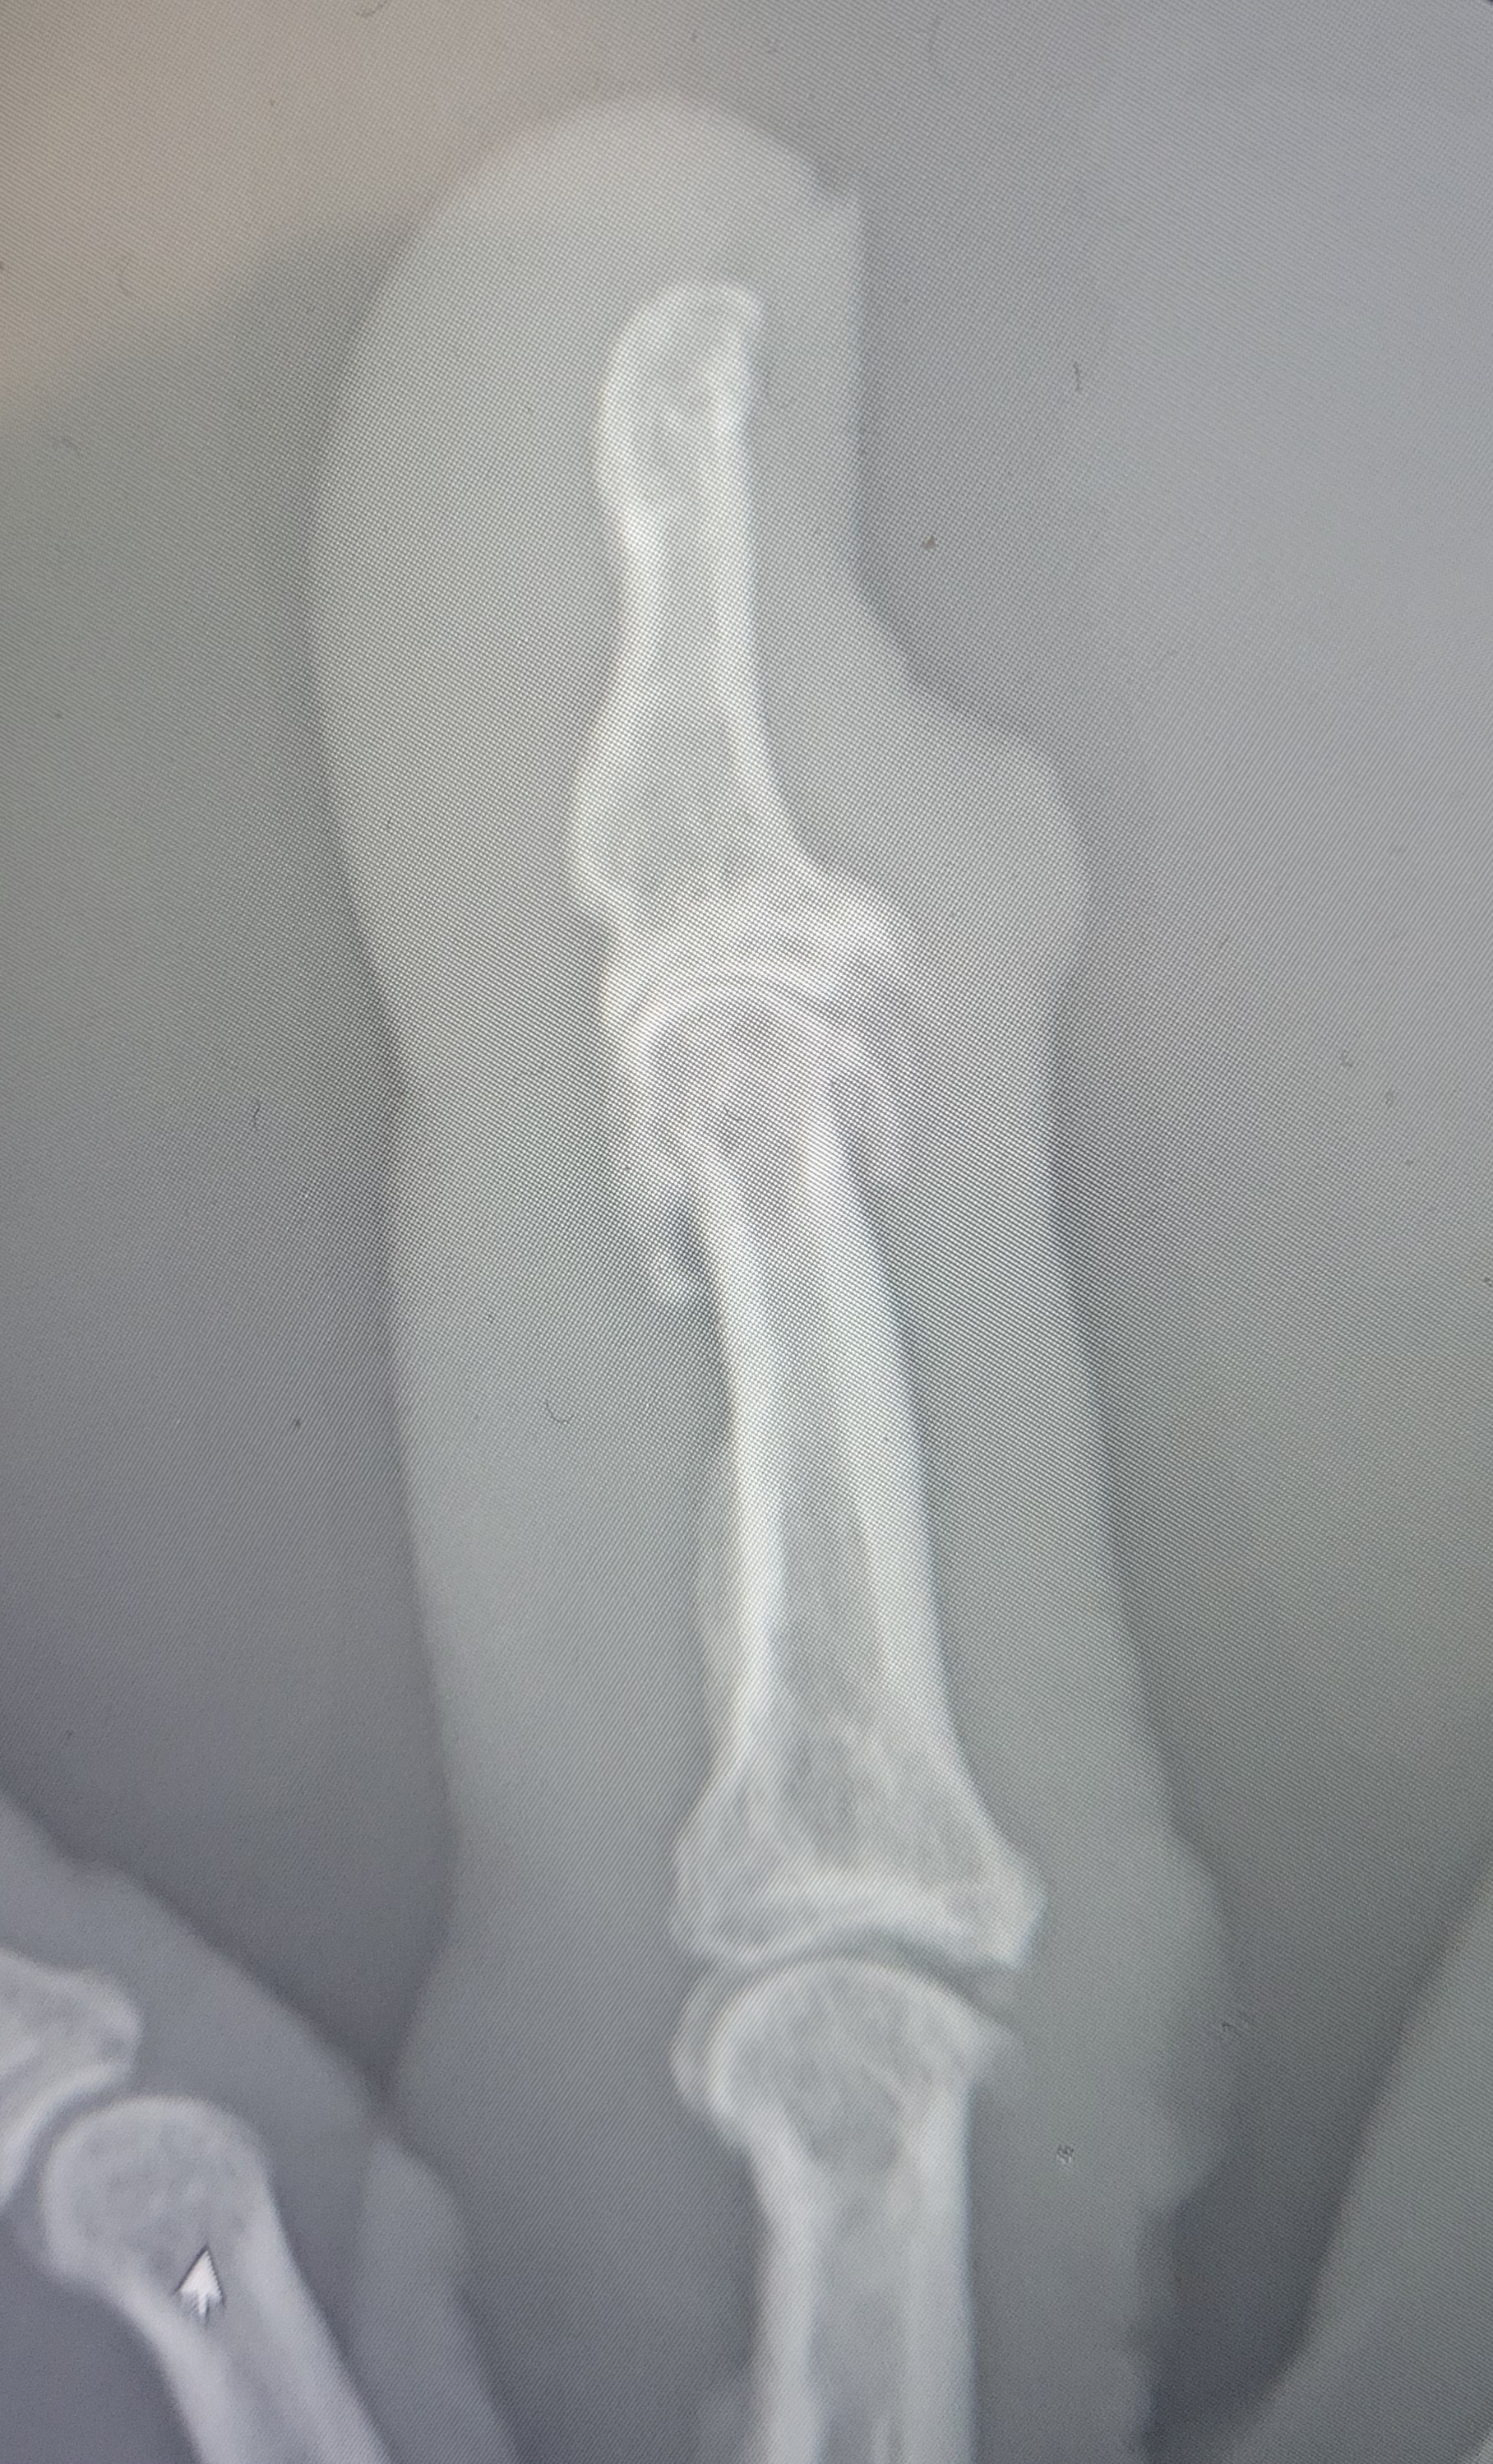

In many cases, the bump turns out to be a simple structure, such as a ganglion cyst, which forms when joint fluid pushes outward. Moreover, bumps in this area can come from mild inflammation, past injury, or everyday repetitive movements. These bumps can get so big that they can rupture and drain sticky fluid which looks like mucus (thus “mucus/mucoid cyst”) but it is actually ganglion cyst fluid - a cousin of joint fluid. Understanding these common causes helps reduce worry and guides next steps.

Moreover, the cyst forms from joint fluid and usually connects to underlying jointrather than anything life-threatening. It may look unusual, but it doesn’t transform into cancer. Understanding this helps ease worry and gives someone confidence to explore treatment options without fear.

Moreover, as the cyst grows, it can press on the nail root and create grooves or visible changes in nail shape. These nail deformities aren’t dangerous, but they can be frustrating, especially when they persist for months. In some cases, the cyst may leak fluid if the skin becomes too thin.